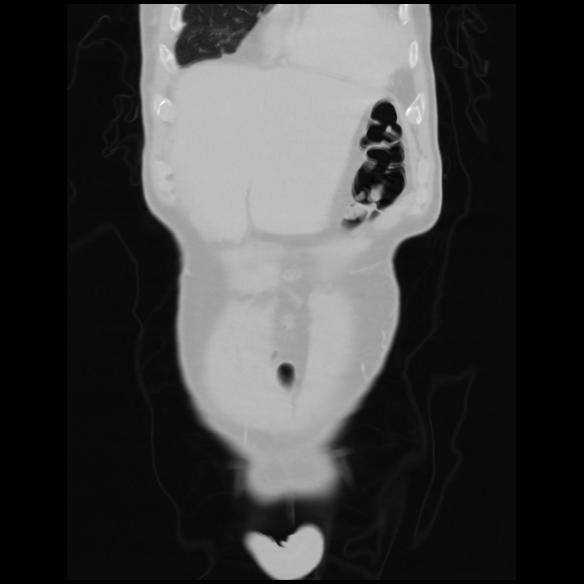

6 CUERPO,CE,Coronal,3.000,CUERPO,Coronal,